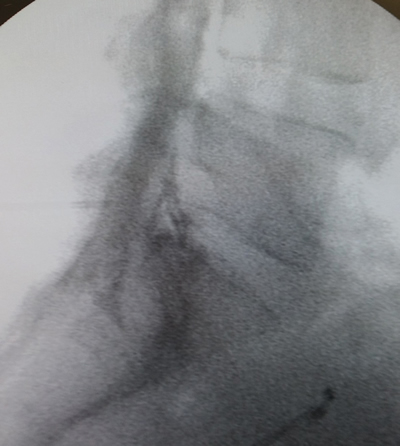

Los procedimientos fueron realizados en sala de operaciones, con anestesia local con lidocaína al 0,5 %, mediante abordaje interlaminar parasagital homolateral al dolor en los espacios L4-L5 o L5-S1, con aguja de Tuohy número 17 o 18, 3½ o 4¾ pulgadas según la complexión física del paciente, con identificación del espacio epidural mediante pérdida de resistencia con suero fisiológico. Se utilizó iopamiron como medio de contraste para visualizar el epidurograma (Figuras 1 y 2).

Fig. 2. Enfoque radiológico lateral de la inyección de contraste en el espacio epidural, durante una inyección epidural de esteroides mediante el abordaje interlaminar parasagital derecho a nivel del espacio L5-S1.